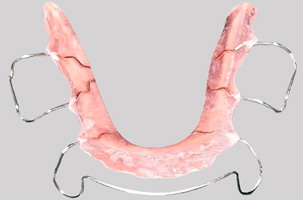

Κινητό μηχάνημα (μασελάκι) αφαιρούμενο - Ορθοδοντικός Δρ. Ζαρμπή

Κινητό μηχάνημα (μασελάκι) αφαιρούμενο:

Αποτελείται από ένα ακρυλικό σώμα και συγκρατητικά σύρματα, διατηρώντας έτσι τα δόντια του στις νέες τους θέσεις.